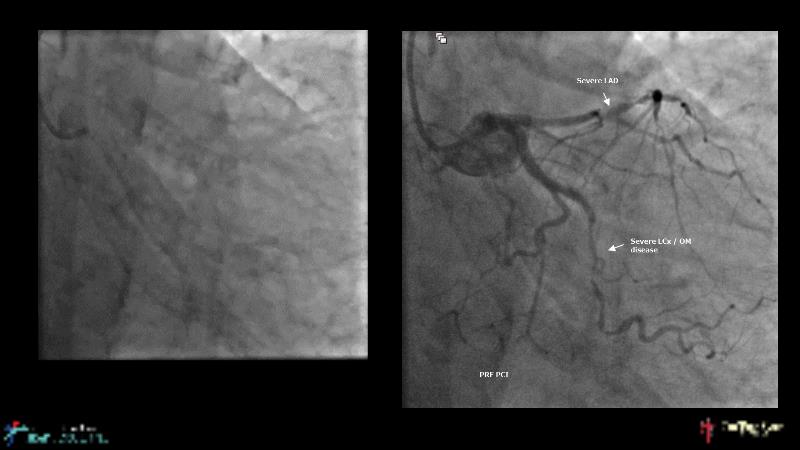

Watch this case-based session to follow discussion about how to choose between DES & DCB, how both can be complementary in diffuse disease as well as in complex PCI, and how physiology and imaging can help guiding PCI, and follow a patient's treatment live.

- To learn the tips and tricks in performing complex PCI intervention with DES and/or DCB

- To discuss cases when DES and DCB are complementary

- To discover strategies to simplify complex PCI cases with the latest DES and DCB